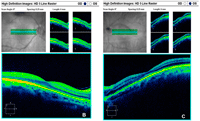

Figura 2). Los hallazgos de tomografía de coherencia óptica de nervio óptico y maculares se comentan en la

Figura 3A,

Figura 3B y

Figura 3C. El fondo de ojo mostraba múltiples y dispersas lesiones ovoideas y alargadas en ambos ojos de color amarillento, que seguían un patrón radial desde la papila hasta periferia ecuatorial (

Figura 3A. Tomografía de coherencia óptica (OCT) de nervio óptico de ambos ojos. Atrofia sectorial superior en ojo derecho y engrosamiento STI para ojo izquierdo.

Figura 3B y 3C. OCT macular para ambos ojos, descarta edema macular, con cambios atróficos en ojo izquierdo.